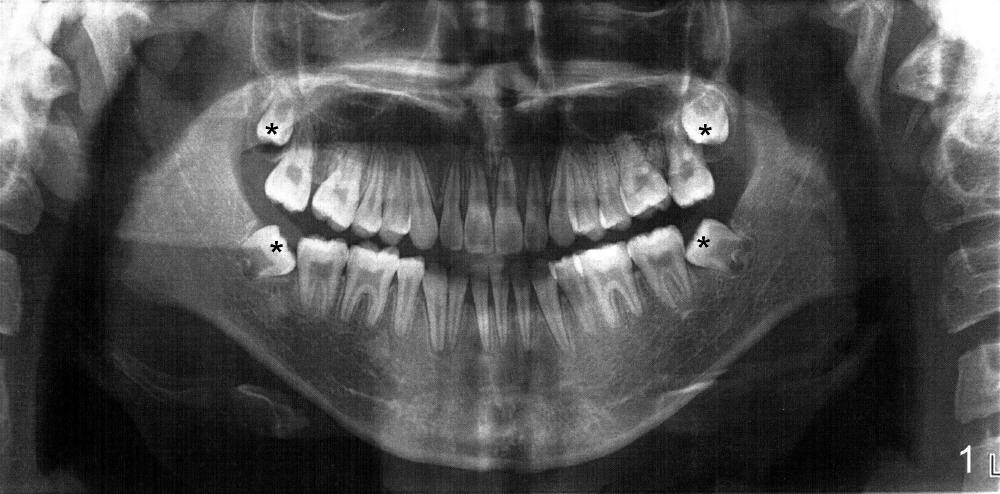

本文讨论如何与口腔专科医生打交道。十五岁男孩由妈妈带来诊所拔除四个智齿(图一:全景片;图二:侧面;图三:咬合正面(3:尖牙)),她说小孩刚刚完成矫正,如果不拔智齿,容易复发。应该拔吗?小孩有点早熟,发育几乎象成人。我该怎么处理?听口矫医生意见?

这是一个很好的病例,我们在每天看病人时常会遇到类似的情况。当你拔牙后,是否发现拔牙似乎帮助不大或还存在一些显出易见的问题,如上颌第二磨牙过度伸长,磨牙咬合不对,你是否想过没有要告诉病人?或者给病人一个自己认为是对病人好的建议或治疗方案?这个病例,我以为正畸治疗效果欠佳,尚需进一步正畸治疗。也许拔除两𠆤上颌第一前磨牙,重新正畸,可将上颌磨牙前移,改善磨牙咬合关系和上颌第二磨牙过度伸长等。当然,要看病人是否理解和愿意进一步治疗。 Maybe it is a new case for you.  Xiao Mu